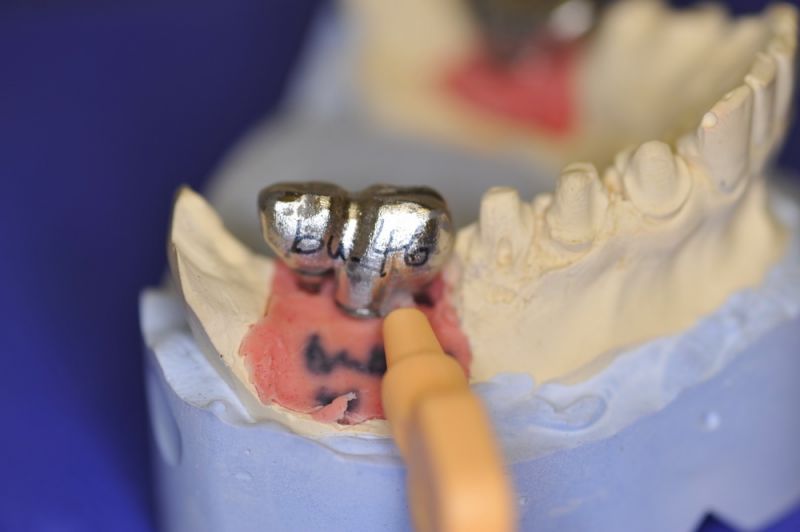

Es war eine Kombination aus Schmerzen bis an die Suizidgrenze, beschränkten wirtschaftlichen Möglichkeiten, sehr stark eingeschränkten Möglichkeiten der für Implantate zur Verfügung stehenden Knochenverhältnisse in einem stark atrophierten Unterkieferseitenzahnbereich und zudem dann auch noch durch auftretenden Problemen bei der Implantatinsertion und nachfolgenden Versorgung der Implantate.

Die Problematik der Implantatversorgungen kann man in einer Analogie folgendermaßen darstellen. Die räumlich beengten Zustände gleichen dem Tanz eines Paares auf einer Briefmarke, und der gleichzeitigen Schritt- und Fusshaltung, dass beim Tanzen die Schuhe geputzt werden können!